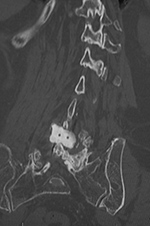

| 85 year-old woman. These images show respectively an AP radiograph of an ILIF at L4-5, an axial CT image of the ILIF, and two coronal reformatted CT images of the ILIF. There is a donar bone plug held in place by the interspinous fixation plate (clamp). |